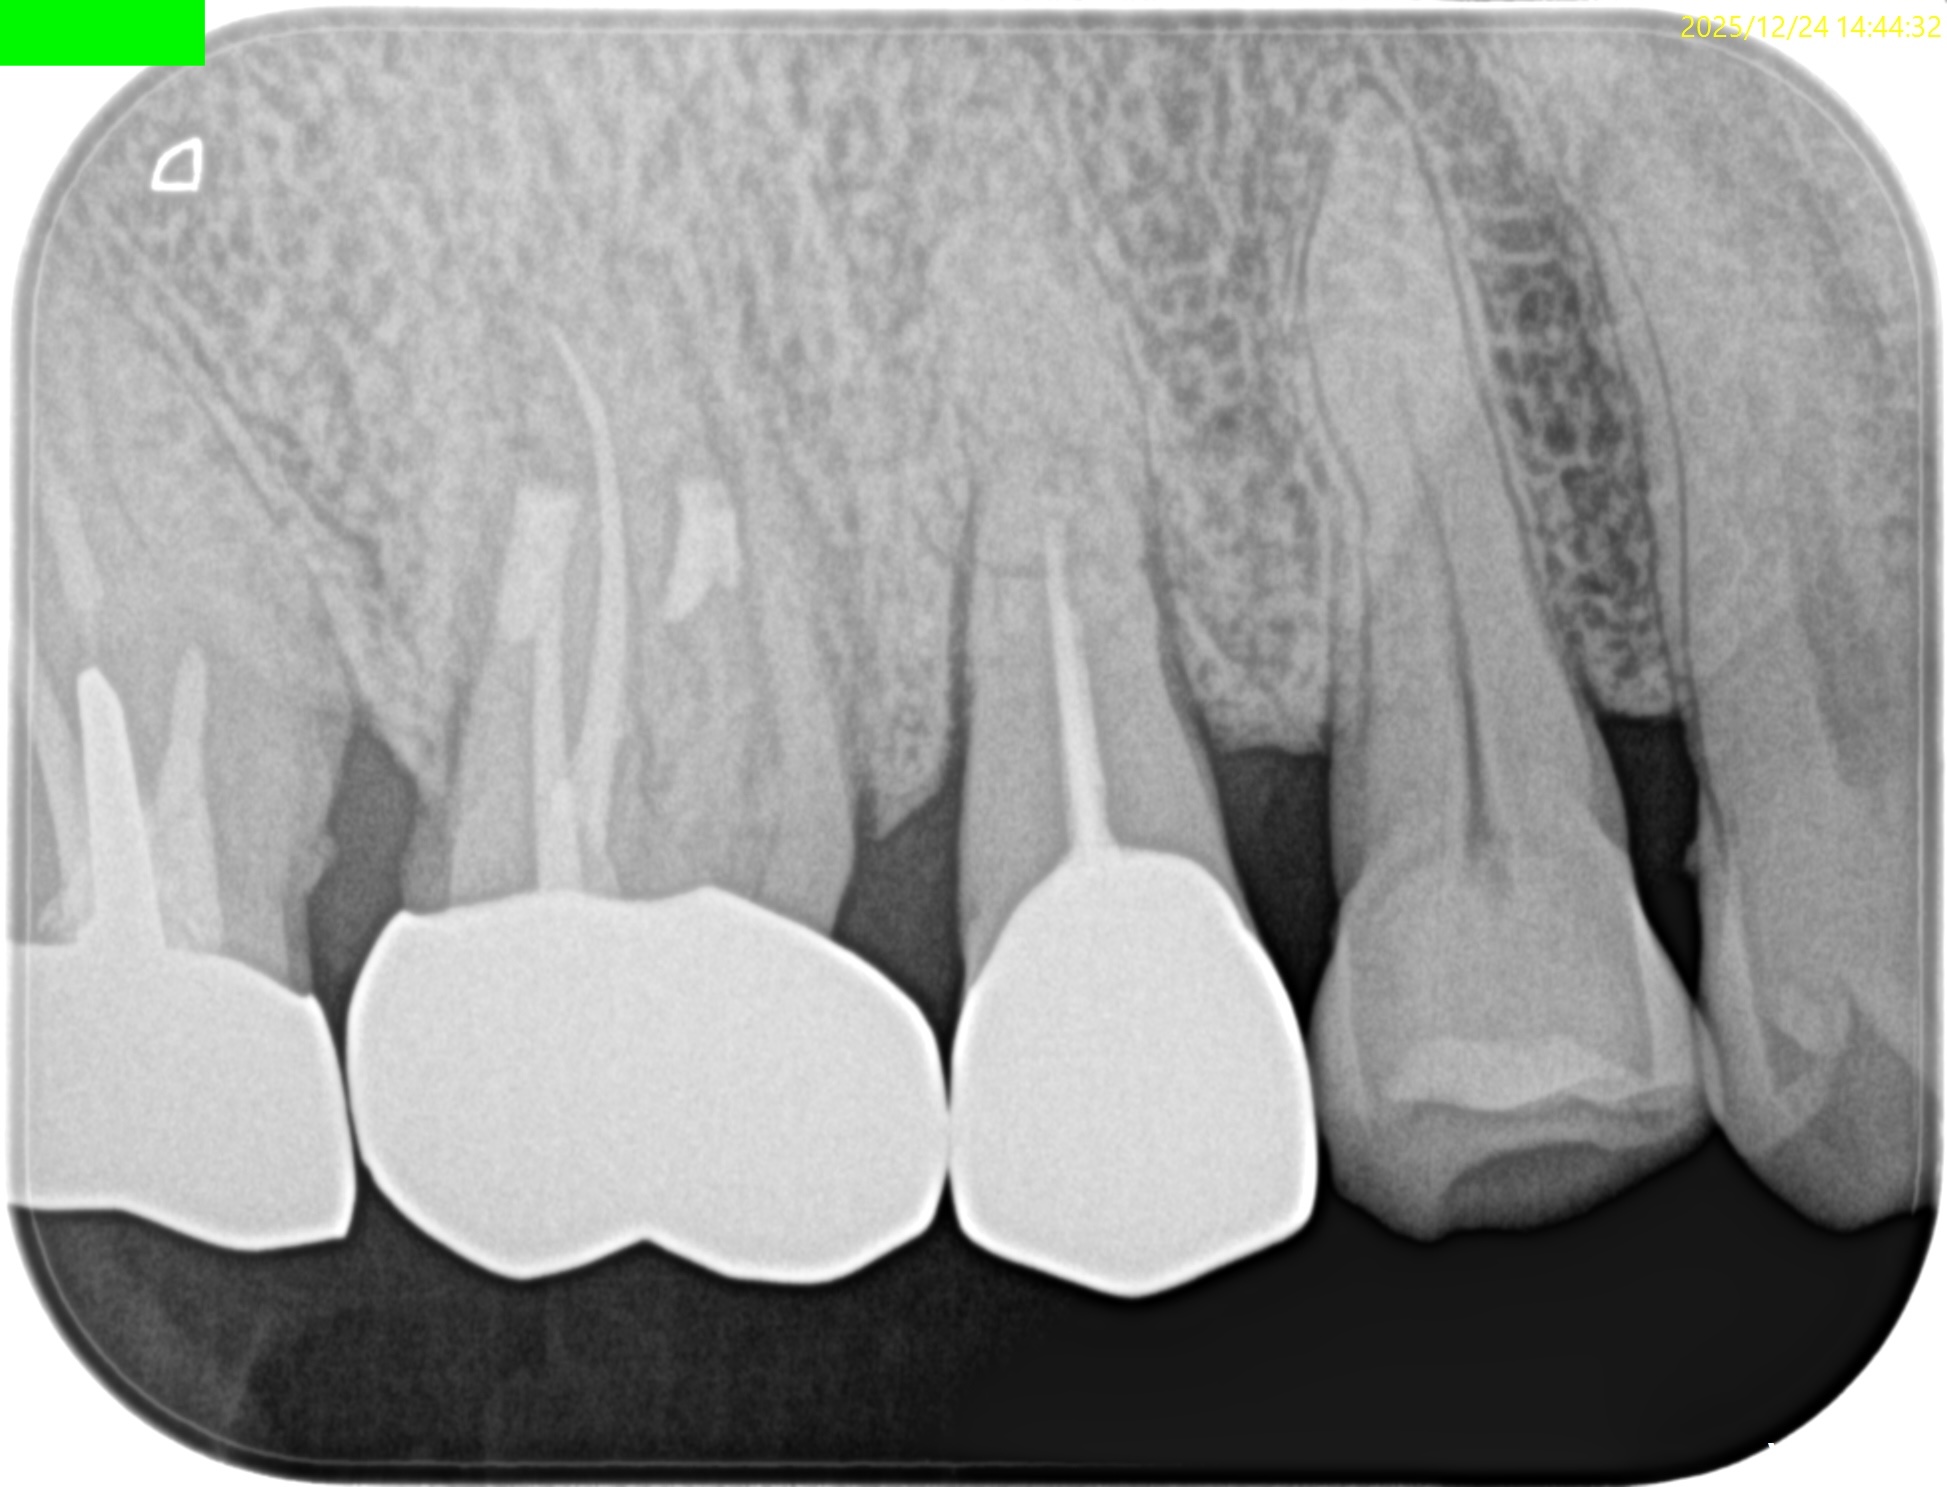

#4 RCT(2025.1.29)

術後にPA, CBCTを撮影した。

ここから1年が経過した。

#4 RCT 1yr recall(2025.12.24)

臨床症状, 術前の歯根膜腔隙の拡大はともに消失した。

ということで、#4の経過観察も終了でいいだろう。